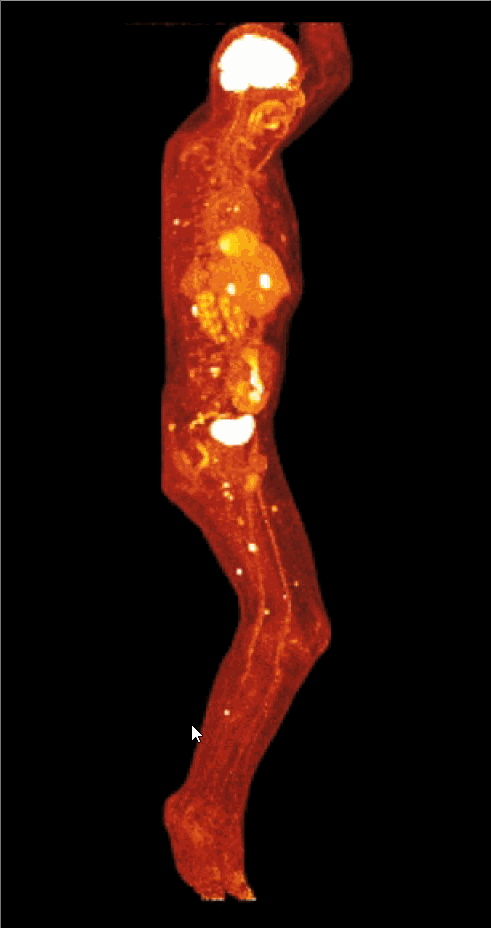

¹⁸F-FDG是葡萄糖的类似物,是临床*常用的显像剂,能反映体内葡萄糖利用状况。将显像剂注入人体后,癌细胞掠去比正常细胞多得多的18F-FDG,但是¹⁸F-FDG仅仅是葡萄糖类似物,肿瘤细胞摄取后不能进一步代谢,能在肿瘤细胞内积聚。随后壹号娱乐 通过PET/CT探测18F发出的γ射线进行定位,就可以让癌细胞“原型毕露”,显示肿瘤的部位、形态、大小、数量及肿瘤内的放射性分布,同时肿瘤细胞的原发灶和转移灶具有相似的代谢特性,一次注射¹⁸F-FDG就能方便地进行全身显像。

四维动图

利用这个原理,PET/CT就能对肿瘤进行诊断、定位、探寻转移灶(分期)、观察疗效,甚至预测患者的生存信息。